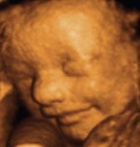

All body systems develop during the first eight weeks after conception6 — before many pregnant women are even aware that they are pregnant!